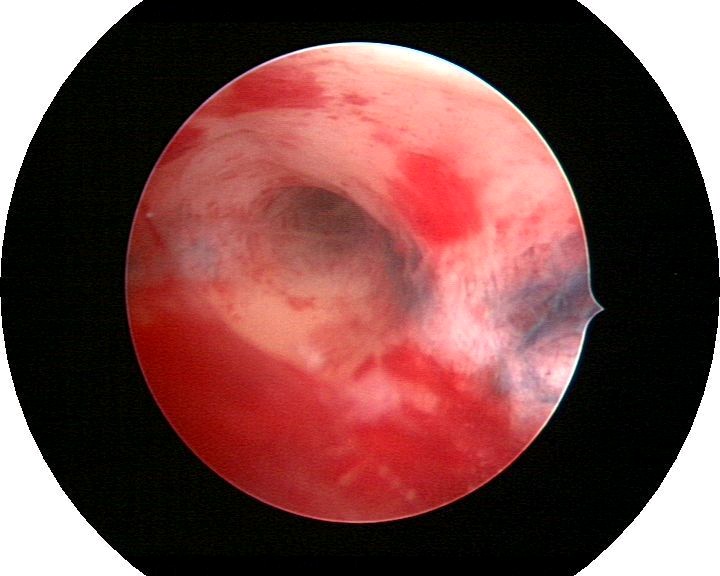

患者35岁,G4P0,2011年4月因继发不孕、月经减少2年,行宫腔镜探查,发现宫腔广泛重度粘连,单极电切分粘,恢复宫腔形态,显露双侧输卵管开口,放置节育环一个,术后月经恢复正常。2011年9月行宫腔镜二探并取环,O型环部分嵌顿,分离残留粘连,宫腔形态正常,双侧输卵管开口可见,同时行腹腔镜下左侧卵巢囊肿剥除术,术中通液双侧输卵管通畅。术后病人及爱人外出旅行,2个月后自然妊娠至足月,2012年7月要求我到其住院医院为其剖宫产,胎盘粘连,出血较多,手术顺利。现49岁,G5P1。